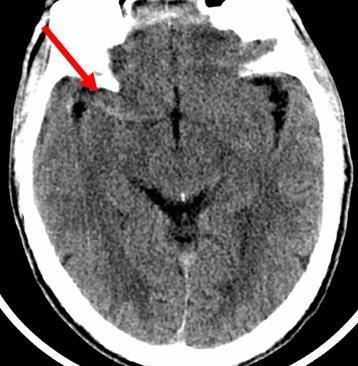

TDM cérébral sans injections : Hyperdensité sur le trajet de l’artère sylvienne (flèche) réalisant une trop belle artère, correspond à un thrombus frais endoluminal (occlusion).Il s’agit d’un signe précoce d’accident ischémique cérébral.